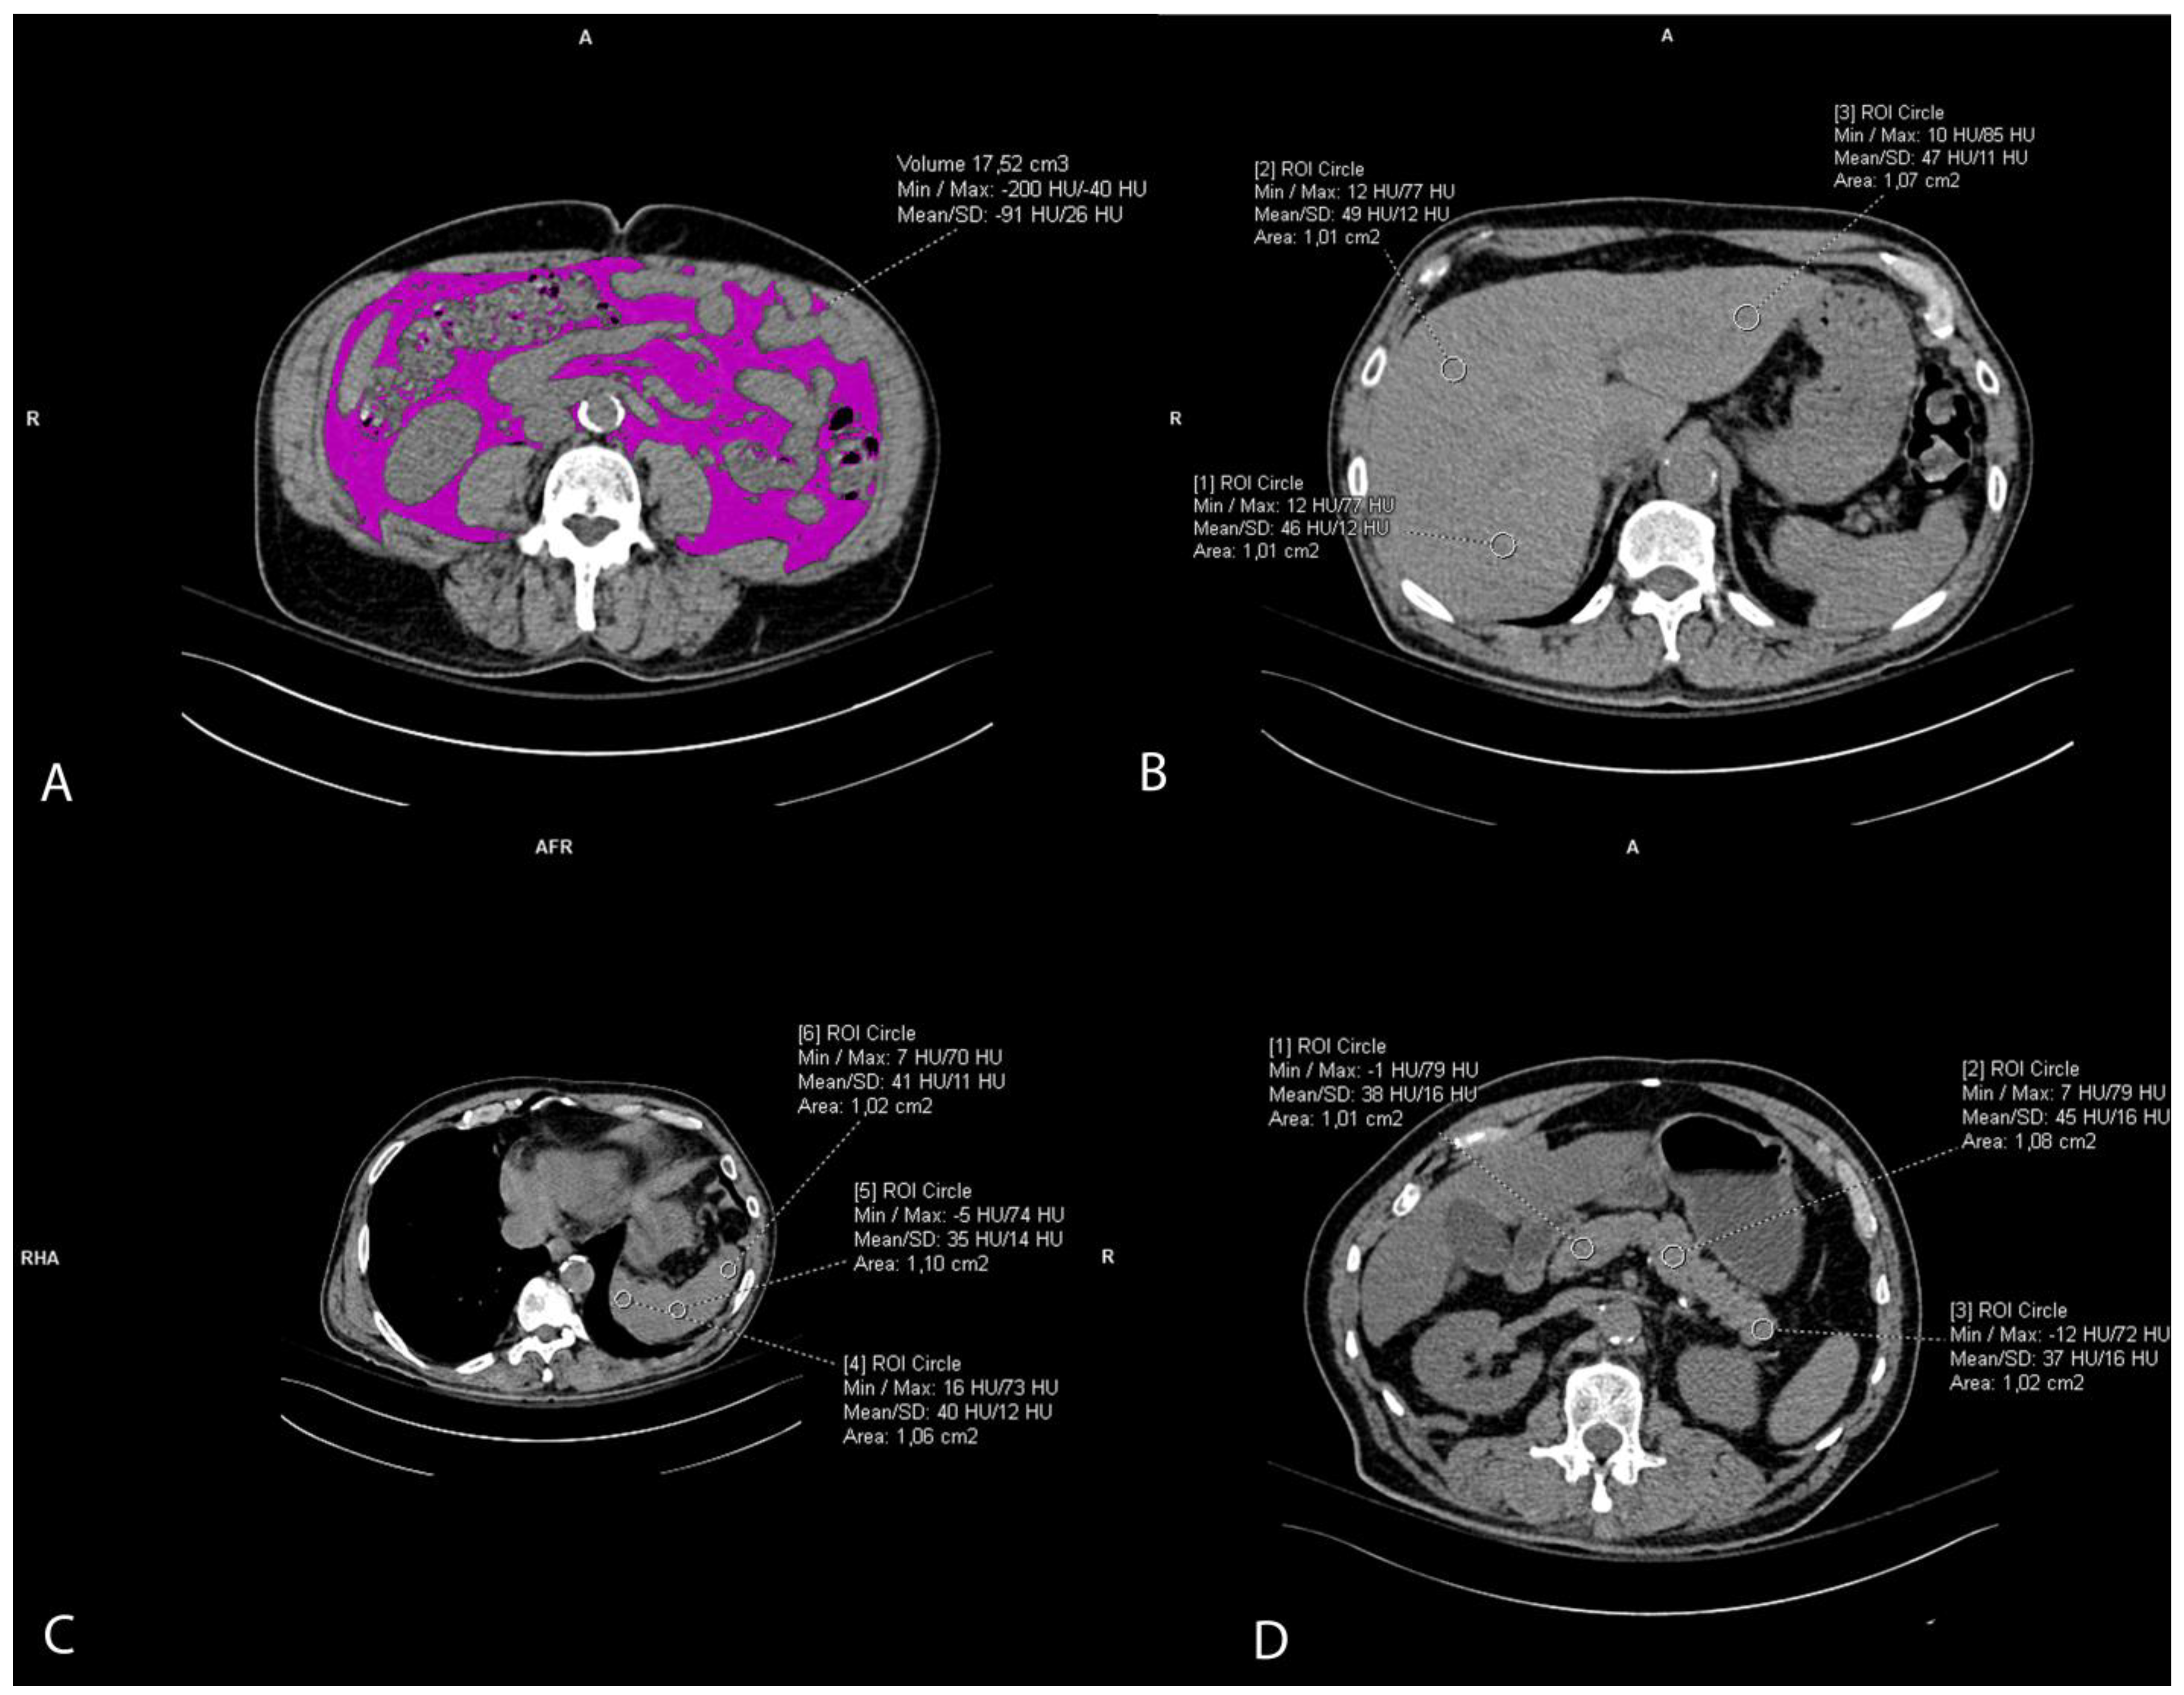

2.3. Visceral Fat Volume Measurement

The visceral fat volume, expressed in cm3, was measured on the native/pre-contrast CT scans of the abdomen and pelvis semiautomatically. First, at the umbilical level, a line at the inner contour of the abdominal muscles was carefully manually drawn. The Hounsfield unit of fat tissue attenuation from −200 and −40 HU was automatically segmented within this area surrounded by the manually drawn line. Finally, the visceral fat volume was automatically calculated by the Siemens syngo.via VB60A_HF08 software (Figure 2A). The intraclass correlation coefficient (ICC) was 0.982 (95% CI 0.96–0.99).

Figure 2. Representative axial CT images showing visceral fat volume estimation (A), liver attenuation measurement (B), spleen attenuation measurement (C), and pancreas attenuation measurement (D).